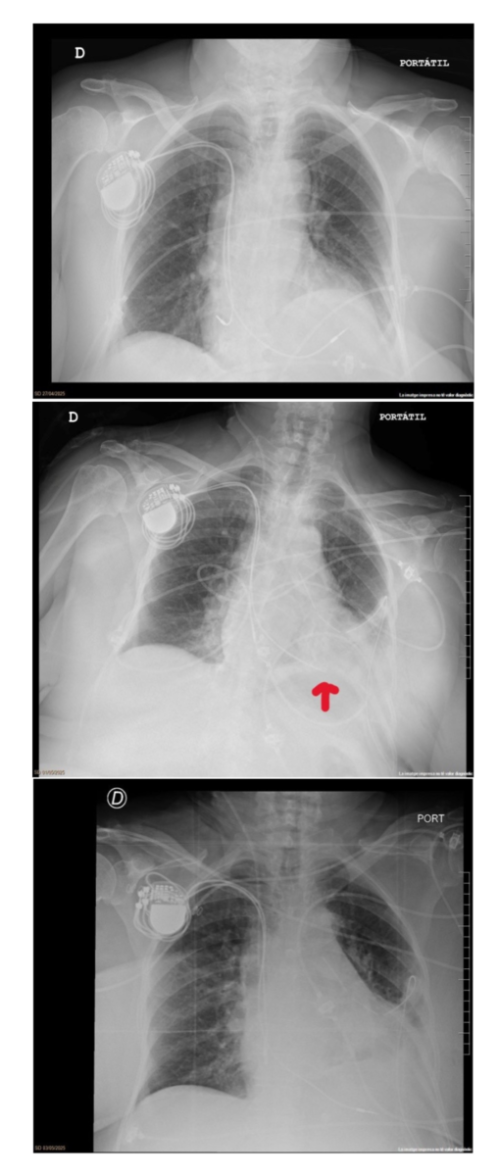

Paciente de 84 años con antecedentes de hipertensión arterial, tuberculosis pulmonar, bronquitis espástica, enfermedad renal crónica y síndrome ansioso-depresivo. Acude a urgencias de otro centro por epigastralgia, donde se implanta MCP por BAV completo. Al día siguiente presenta fallos de captura y es derivada a nuestro centro. Ingresa en la Unidad de Cuidados Cardíacos Agudos (UCCA), donde mediante pruebas de imagen se evidencia perforación por cable de MCP, estando 3,2cm extracardíaco en la pared posterior costal y con sangrado de la arteria intercostal. Se realiza toracotomía anterior con reparación de la herida cardíaca y drenaje de 1’8 litros. A los tres días se realiza retirada total del cable y colocación de nuevo electrodo ventricular.

Figura 1. Perforación electrodo; electrodo cortado; nuevo electrodo bien posicionado